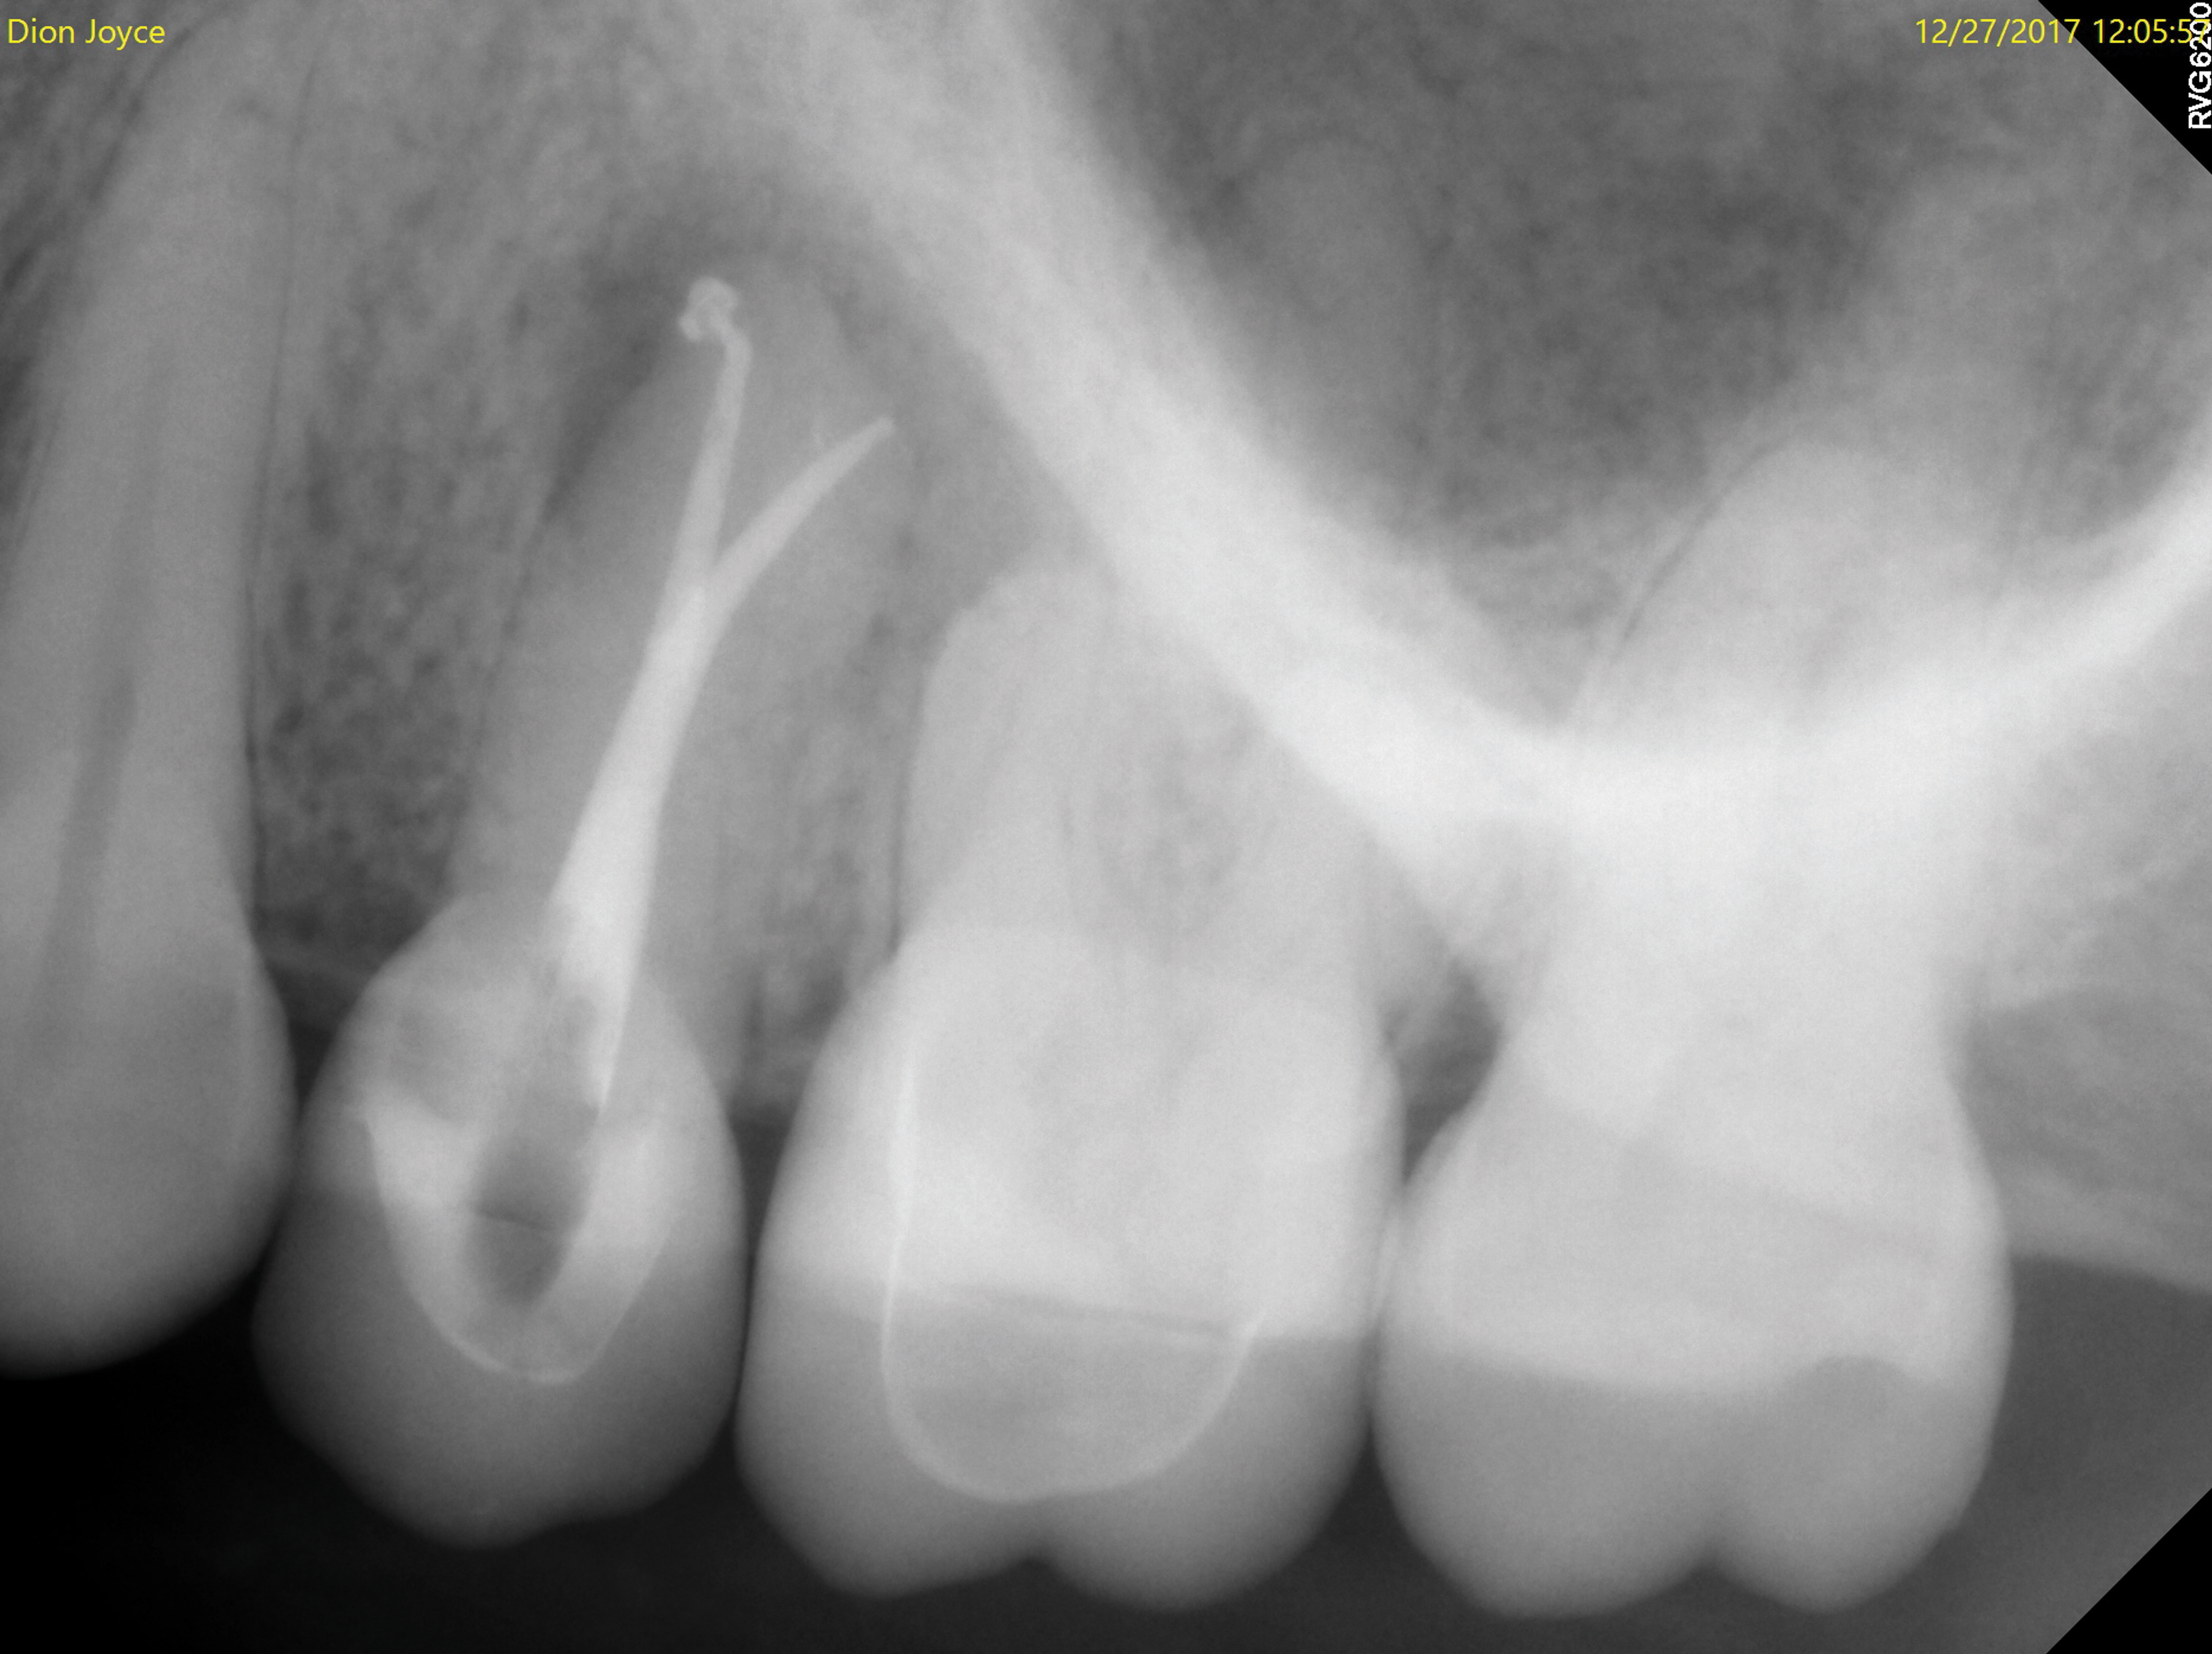

Periapical and CBCT imaging confirmed the presence of apical pathology, as well as a dramatic sinus communication with MSEO (Figure 1 and Figure 2). The diagnosis for tooth No. 13 was pulpal necrosis with asymptomatic apical periodontitis. NSRCT was completed (Figure 3). At the patient's 1-year follow-up appointment, tooth No. 13 remained asymptomatic, her sinusitis was resolved, and complete radiographic healing of both periapical pathology and the MSEO was noted (Figure 4).

The diagnosis for tooth No. 14 was pulpal necrosis with asymptomatic apical periodontitis. NSRCT was completed (Figure 9), followed by full-coverage restorative care performed by the general dentist. A 3-month follow-up revealed resolution of prior sinus symptoms, normal clinical findings, and healing radiographic pathology, including periapical pathology and associated maxillary sinus mucositis (Figure 10 and Figure 11).

Both of these cases illustrate the improvement in sinus pathology findings from preoperative CBCT scans to postoperative recall CBCT scans following NSRCT (Figure 4, Figure 10, and Figure 11). In addition, in both instances the re-establishment of the previously obliterated cortical boundary between the apex and maxillary sinus was impressive. Clinically, the resolution of sinusitis symptoms in both patients after receiving nonsurgical endodontic therapy was quite notable. Despite the absence of specific dental pain, these patients' sinusitis symptoms could not have been alleviated without the endodontic interventions due to the odontogenic etiology of their disease. These two cases demonstrate the pivotal role of CBCT imaging in diagnosis and recall as well as the success of NSRCT when treating cases of MSEO.

Fig 4. One-year recall CBCT. Note resolution of prior periapical pathology on tooth No. 13, sinus communication, and MSEO.

Figure 4

Fig 10. CBCT imaging at 3-month follow-up showing signs of healing and decrease in maxillary sinus mucositis. Fig 10: Sagittal view, buccal roots No. 14. Fig 11: Sagittal view, palatal root No. 14.

Figure 10

Fig 11. CBCT imaging at 3-month follow-up showing signs of healing and decrease in maxillary sinus mucositis. Fig 10: Sagittal view, buccal roots No. 14. Fig 11: Sagittal view, palatal root No. 14.

Figure 11